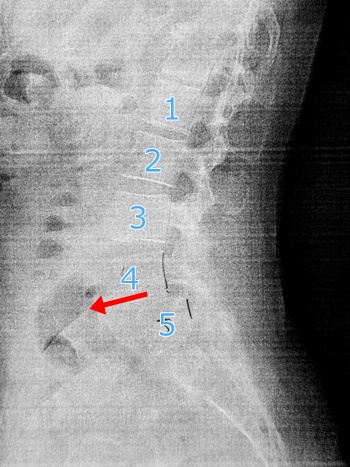

ちなみに紙にプリントしてもらったレントゲン写真、ちょっと見にくいけど横から背骨を見たところ。脊椎の4番が前にすべってるそうです。たしかにすべってるかも。

なんか知らんけど痛そう。そして前かがみのレントゲンがもっと痛そう。

すべってるすべってる(笑) 先生いわく